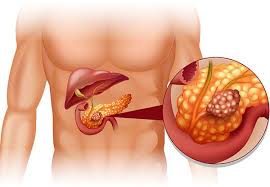

قیمت: 32٬000 تومان - دسته بندی فایل: علوم پزشکیپاورپوینت پانکراتیت حاد

فروش ویژه پاورپوینت حرفه ای پانکراتیت حاد با تخفیف استثنایی فقط 44 هزار تومان تعداد اسلاید: 20 اسلاید